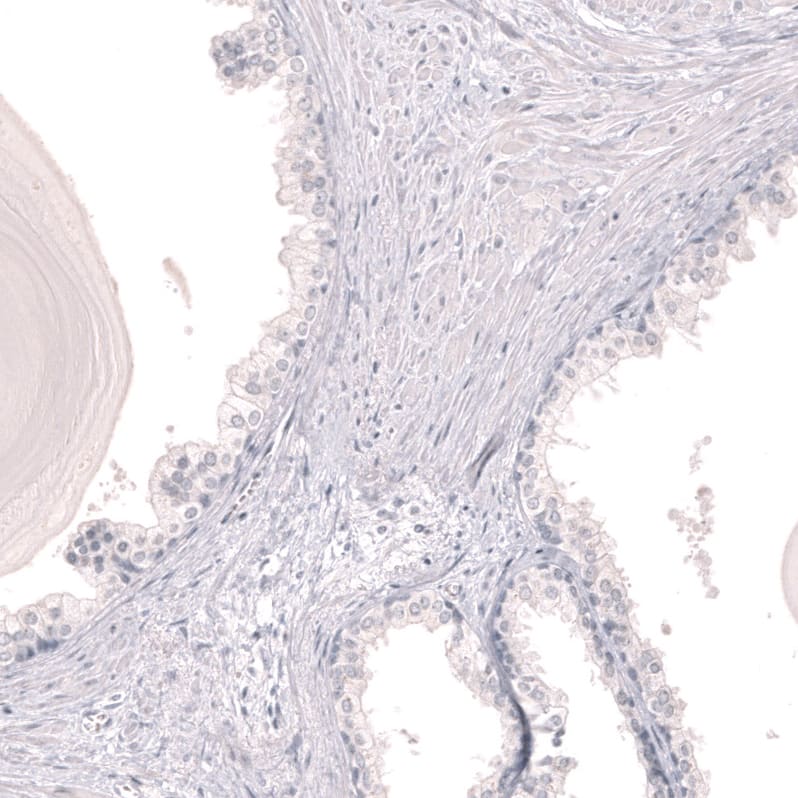

Staining of human skeletal muscle shows no positivity in myocytes as expected.